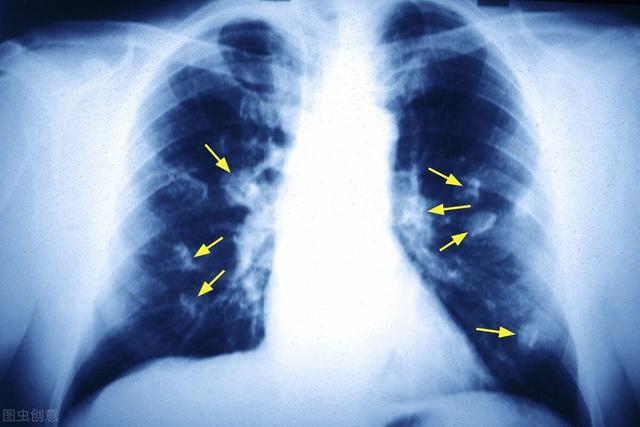

矢印は結節を指しているが、2016年3月に発見されたときは約0.5cmと非常に小さかったが、今では定期検診でこのように非常に多くの結節が見つかっている。画像で良性か悪性かを判断する方法はなく、検討するという選択肢しかなく、検討と経過観察も最良の手段である。

結節は腫瘤(3cm以上)に変化しており、この肺がんは教科書的なもので、基本的に肺がんを支持する悪性腫瘍の兆候をすべて備えている。不規則な境界、小葉、バリ、胸膜の引きつれの徴候。